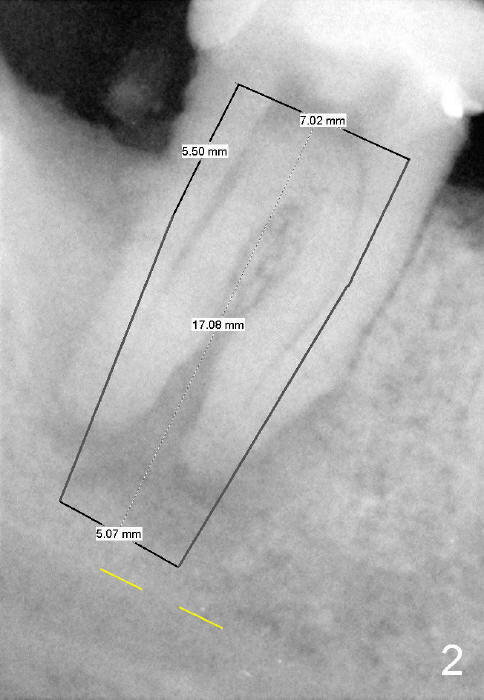

The tooth #31 of a 38-year-old lady has endo perio disease (Fig.1). Due to the large periapical lesion, there will be no solid (new) bone available for primary stability of an immediate implant (Fig.2: 7x17 mm). Yellow dashed line represents the upper border of the Inferior Alveolar Canal (IAC). Infiltration anesthesia is administered first. The mesiodistal widths of the root of the extracted tooth are 10 and 7 mm at the coronal and apical ends, respectively; the buccolingual ones 7 and 5 mm; the length 17 mm (Fig.3). The socket appears much larger than the root (Fig.4). To prevent paresthesia, no drills are used. Instead, a series of tap drills (6,7,8x17 mm) are sequentially inserted into the socket. The largest tap (Fig.5 T; 8x17 mm) binds to the socket securely with separation from IAC. Block anesthesia has to be administered before removal of the tap. A tapered implant (8x17 mm) is placed with insertion torque greater than 60 Ncm (Fig.6 I); allograft mixed with Osteogen is placed around the implant (*). Collagen dressing covers the opening of the remaining socket. The wound is protected with perio dressing, which is partially secured by an abutment (A in Fig.6). No paresthesia is reported by the patient a few hours postop.